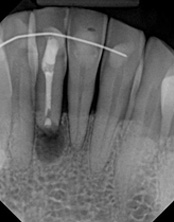

In this situation, some would say the canals are so “calcified” that root canal treatment can’t be done; or sometimes the canal can’t be found. And because of that the tooth would need an extraction and an implant. In some instances, root canal therapy can’t be done but that does not mean the tooth is a loss. The solution is micro-apical surgery, an apicoectomy.

This person had root canal therapy many years ago. One root had excess material outside of the root preventing healing. Another root had a perforation (a hole) and a crack. The large root had a post and had not healed from the initial root canal treatment.

The post was removed, that root was retreated. The root with the excess material, an apicoectomy was done, the excess material, and infection cleaned out. The root with the perforation and crack was removed. The tooth healed and is still in function. This area is a poor area for an implant.